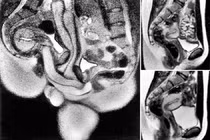

Bệnh nhân sau đó ngã xuống đất không bị thương nhưng nữ y tá lại không thể thoát ra. Khi chiếc giường bị hút vào trong máy chụp MRI và mắc kẹt lại, nữ y tá bị rách sâu và hai chiếc đinh vít cắm vào cơ thể cô.

Nữ y tá bị thương sau đó cho biết, khi xảy ra tai nạn, cô đã cố gắng chạy và vùng vẫy một cách tuyệt vọng, nhưng lực hút quá mạnh khiến cô không thể thoát ra ngoài. Khi được cứu thoát, nữ y tá bầm tím khắp người, có chỗ bị thương sâu. Trải qua phẫu thuật, hai chiếc đinh vít cắm vào cơ thể cô cũng được lấy ra.